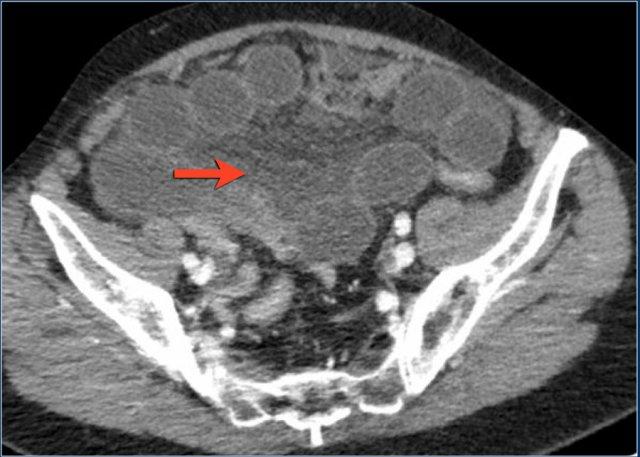

Đây là một trường hợp tắc ruột quai kín khác.

Lưu ý sự khác biệt về mức độ ngấm thuốc giữa các quai ruột bình thường không giãn (mũi tên xanh lá) và các quai ruột giãn bị thắt nghẹt (mũi tên đỏ).

Ở trung tâm là các mạch máu mạc treo bị xoắn vặn (mũi tên vàng).